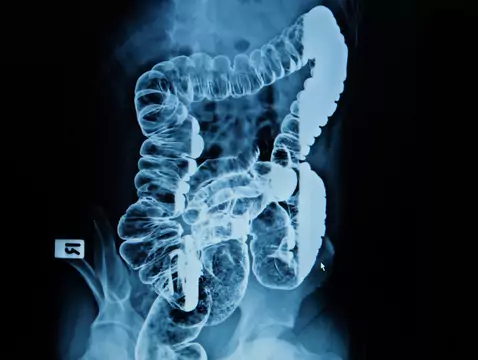

Kolonoskopia to nieoceniona wręcz metoda diagnostyczna, aby jednak badanie to rzeczywiście wniosło coś do procesu diagnostycznego, jest jednak konieczne spełnienie pewnego warunku. Otóż przed...